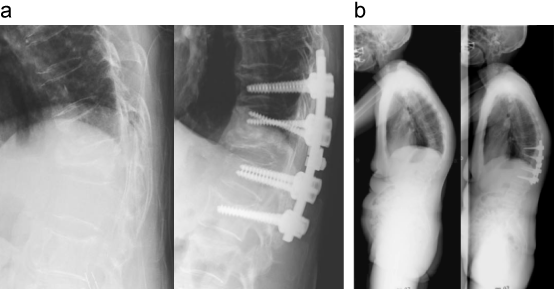

椎体骨折後後弯変形に対する後方矯正骨切り術

後方矯正骨切り術により、脊椎の矢状面バランスが改善された。

a:術前後胸椎X線側面像

b:術前後全脊柱X線側面像

出典

img

1: 著者提供